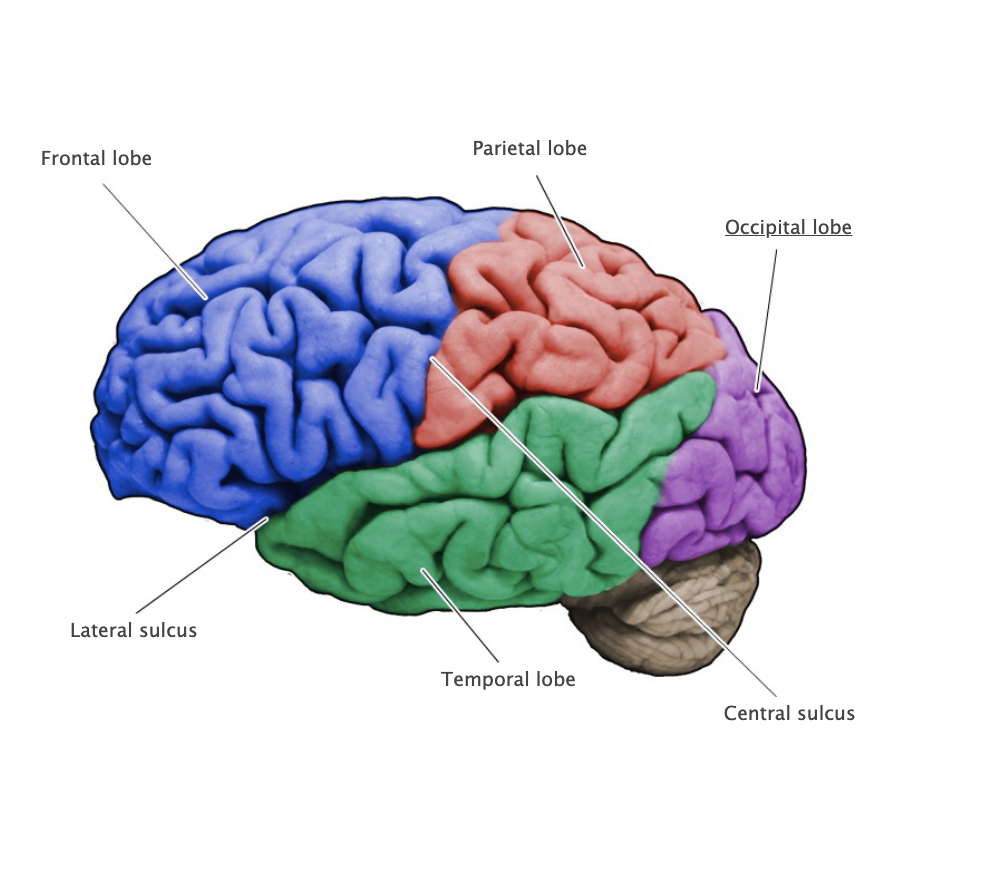

Central Sulcus

A prominent sulcus on the dorsal-lateral aspect of the cerebral hemispheres formed by that precentral and postcentral gyri, this sulcus defines the boundary between the frontal and parietal lobes.

Parietal lobe

Region of the cerebral cortex posterior to the central sulcus, anterior to the occipital lobe and superior to the lateral fissure; involved in somatic sensation and numerous complex functions, including multimodal proprioception, language comprehension, attention, and spatial awareness.

Occipital lobe

Most posterior of the four lobes of the cerebral hemisphere and is primarily involved in visual functions.